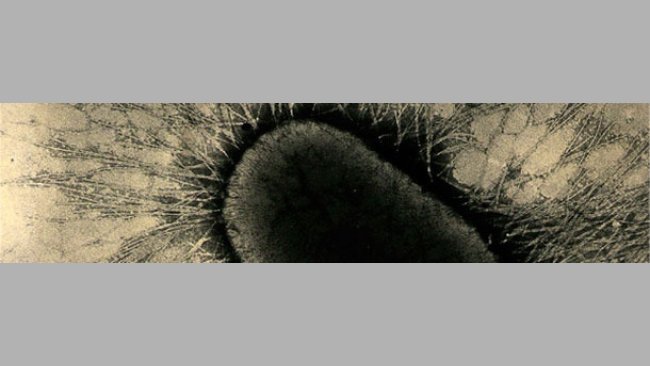

- Positive : association causale forte si on est capable de démontrer des lésions intestinales avec E. coli adhérant aux cellules épithéliales.